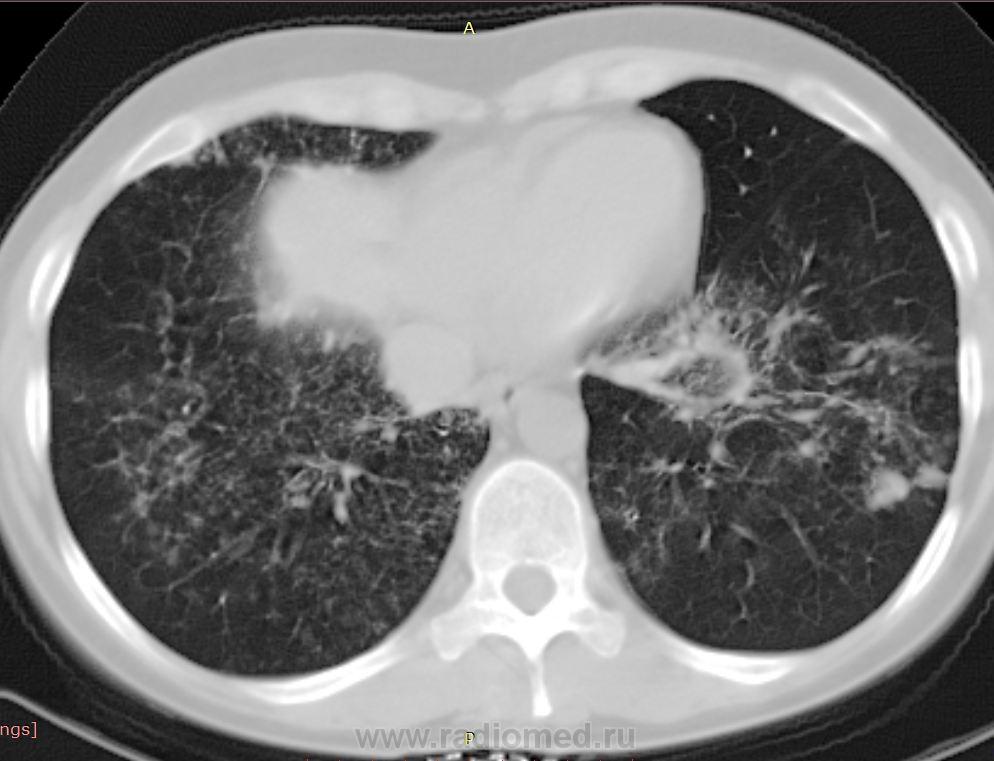

38 лет. 6 лет назад cr носоглотки. Лучевая и химиотерапия. С июля 2012 г. клиника бронхолегочного заболевания.

Узелки хаотичного распределения (туб, микозы, мтс). Участки, напоминающие дерево-в-почках. На верхушках посттуберкулезный фиброз, при этом верхние отделы, насколько можно судить, чистые. Прикорневой фиброз и тракционные бронхоэктазы нижних отделов. Преобладание процесса в нижних долях + фиброзные изменения, +  утолщение??? междолькового интерстиция. Значимой лимфаденопатии не нашла, выпота тоже.

На первое место - неспецифическая интерстициальная пневмония. Спецпневмофиброз верхушек. Насколько возможна реактивация туберкулеза прогнозировать не берусь.

Присоединюсь к ЛГ (со всеми ее оговорками): ДИЗЛ, неспецифическая интерстициальная пневония, участки фиброза, бронхиолита.

Хотелось бы увидеть КТ в другом окне. По-моему, за онко ничего нет, больше всего склоняюсь к саркоидозу. Обширность поражения от верхушек к куполам. Да и участки фиброза в верхушках видел неоднократно, писали , что ТБЦ, а оказывалось саркоидозом. Единственно, смущают бронхоэктазы.

бронхоальвеолярная карцинома, а еще напоминает лимфангический карциноматоз.